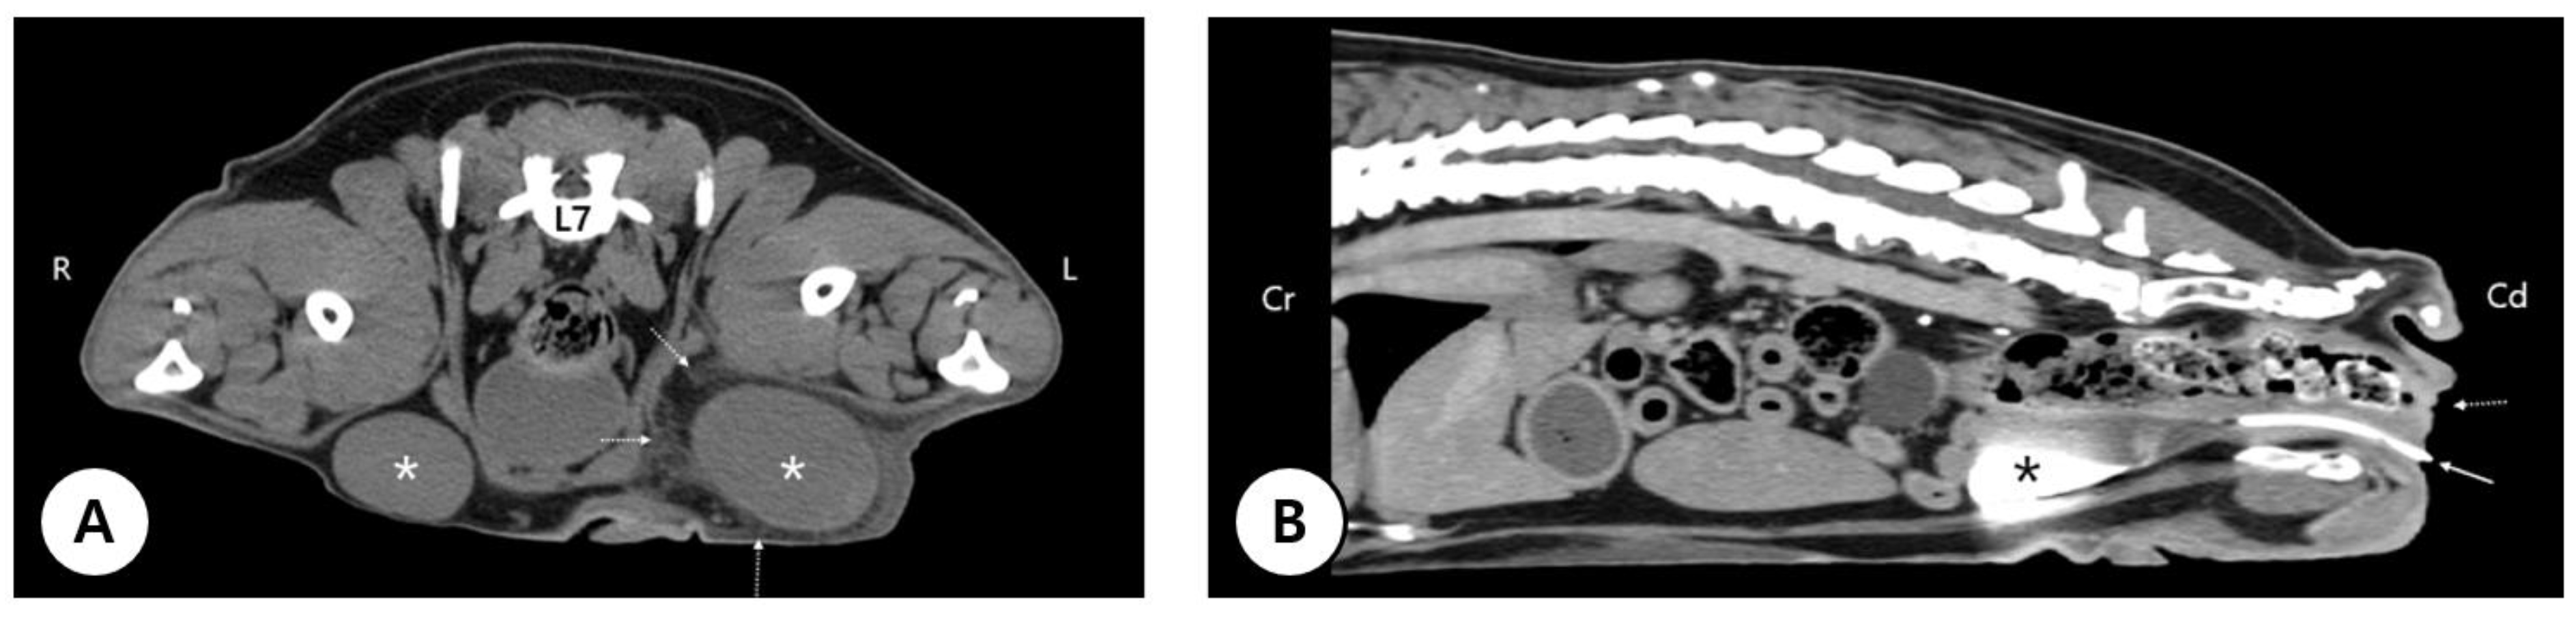

3.1. Clinical Presentation and Long-Term Conservative Management of Severe Perineal Hypospadias